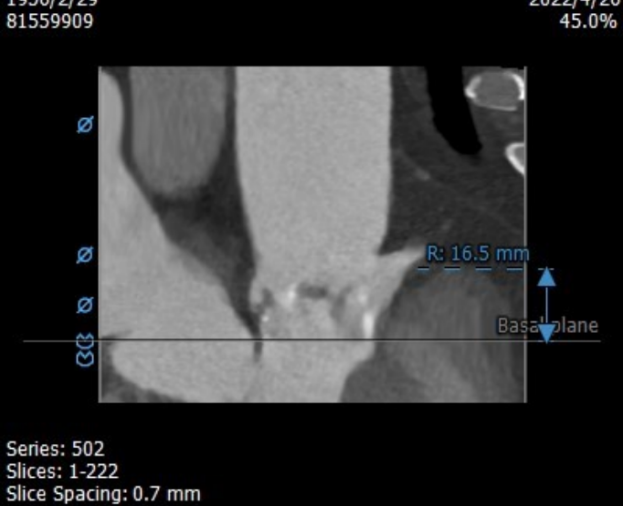

左冠开口高度13.0mm,右冠开口高度16.5mm,双侧冠脉开口未见明显附壁钙化,结合瓦氏窦宽度和瓣叶长度综合判断冠脉阻挡风险较低。

升主内径36.0mm,主动脉瓣环与水平面夹角39°,主动脉弓角与弓距可。